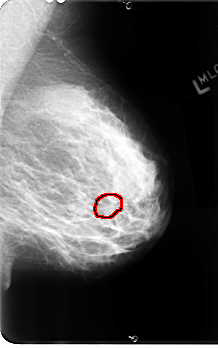

B_3111_1.LEFT_MLO

LEFT_MLO LINES 4864 PIXELS_PER_LINE 3040 BITS_PER_PIXEL 12 RESOLUTION 50 OVERLAY

FILE: B_3111_1.LEFT_MLO.OVERLAY

TOTAL_ABNORMALITIES 1

ABNORMALITY 1

LESION_TYPE CALCIFICATION TYPE AMORPHOUS DISTRIBUTION CLUSTERED

ASSESSMENT 4

SUBTLETY 3

PATHOLOGY BENIGN

TOTAL_OUTLINES 1

BOUNDARY